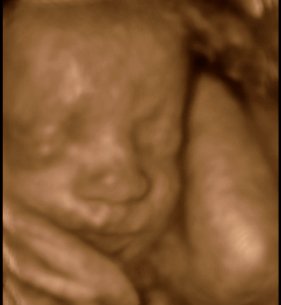

Da jeg snakkede med hende i dag sagde hun at fra uge 27 til og med uge 31 var det bedste tidspunkt at få det gjort....

Vi skal give 1400 kr for 45 minutters total gennem scanning, hvor hun fortæller, undersøger babyen fra top til tå, laver vægtskøn også får vi billeder og dvd med hjem.... Og ja det er da mange penge, men min forlovede har haft en masse vikar timer den her mdr, også sagde han at han syntes vi skulle bruge de penge på noget vi normalt ikke ville have gjort. Han sagde egentlig at jeg kunne gå ud og shoppe for dem, men jeg har termin om ti uger, så gider ærlig talt ikke bruge penge på nyt graviditets tøj, så hellere det her som vi egentlig havde valgt fra pga prisen, men som vi begge to rigtig gerne vil....